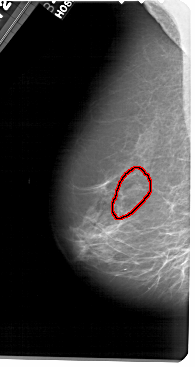

A_1651_1.LEFT_CC

FILE: A_1651_1.LEFT_CC.OVERLAY

TOTAL_ABNORMALITIES 1

ABNORMALITY 1

LESION_TYPE CALCIFICATION TYPE PLEOMORPHIC DISTRIBUTION LINEAR

ASSESSMENT 4

SUBTLETY 1

PATHOLOGY BENIGN

TOTAL_OUTLINES 1

BOUNDARY